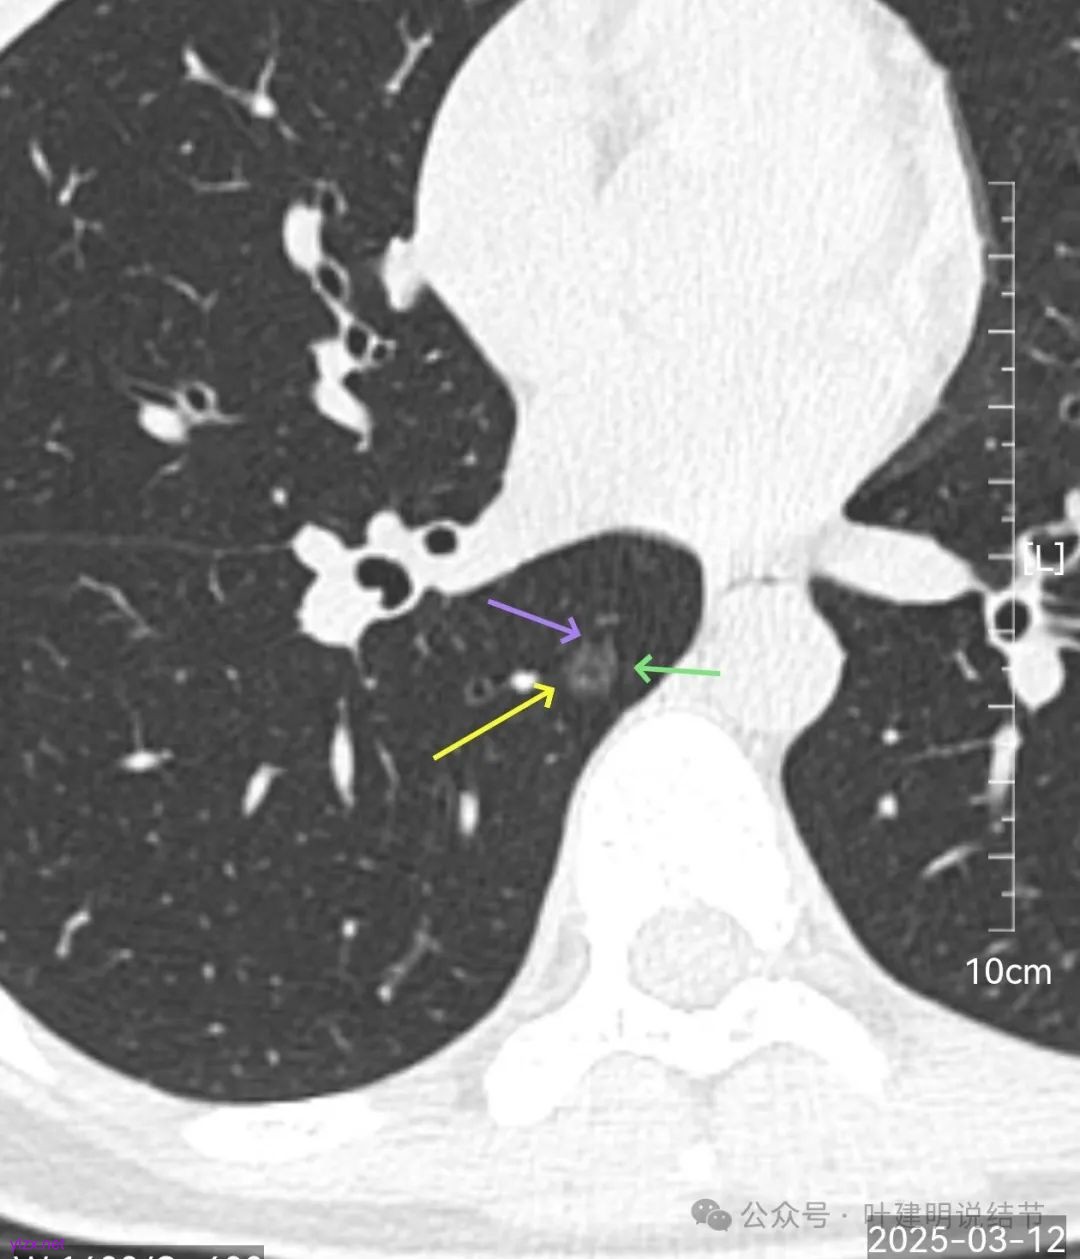

再来看风险最大的病灶6的连续层面:

血管从旁过,没有受结节影响。